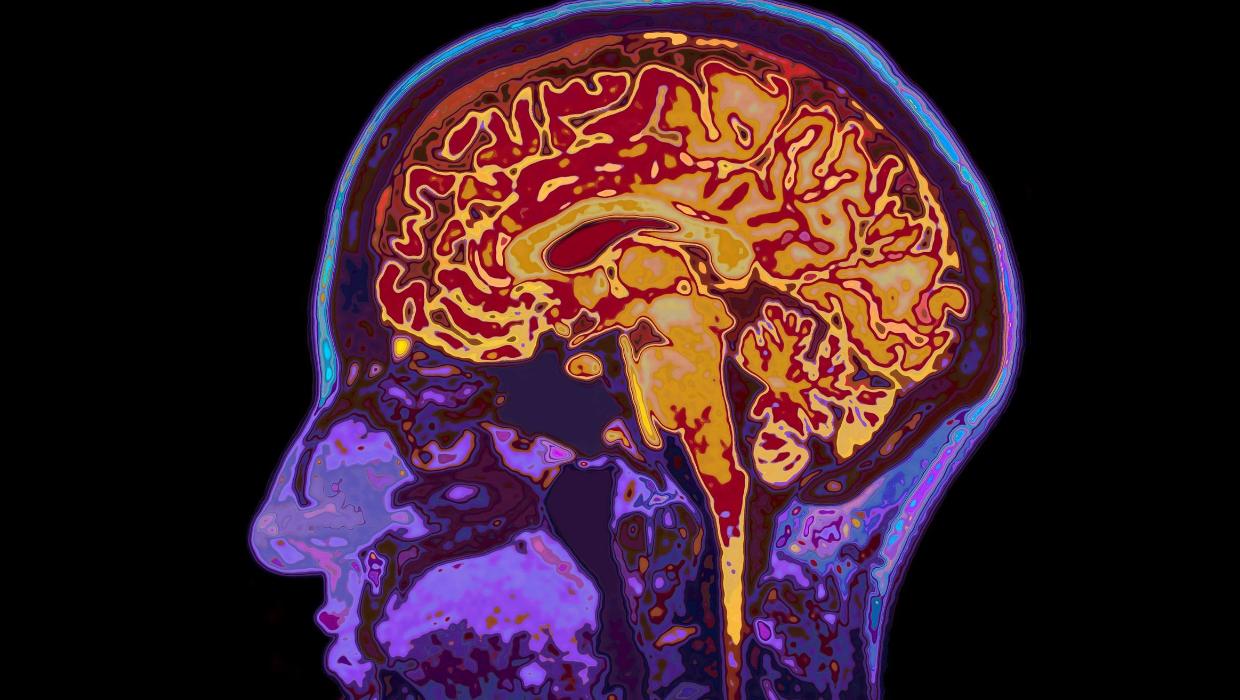

A recent study conducted by researchers at the University of Cambridge has unveiled significant insights into brain development, suggesting that the human brain remains in a state of adolescence until the age of 32. This research identifies five major epochs of brain growth, highlighting four crucial turning points throughout a person’s life.

The study, published on March 15, 2024, marks a pivotal advancement in our understanding of how the brain evolves. By analyzing various developmental stages, researchers have delineated the periods of brain maturation that can influence cognitive abilities, emotional regulation, and decision-making skills.

According to the findings, the first epoch begins in early childhood and continues until approximately age 12. This period is characterized by rapid neural growth and the establishment of fundamental cognitive skills. Following this, the second epoch spans from ages 12 to 18, encompassing the turbulent teenage years when individuals often experience heightened emotional changes and social interactions.

The third epoch extends from ages 18 to 25, a time when the brain begins to refine its connections, leading to improved reasoning and judgment. The study highlights that during this phase, individuals are more likely to explore different identities and life paths.

The fourth epoch transitions from age 25 to 32, during which the brain reaches a more stable state, allowing for enhanced self-regulation and maturity. Finally, the fifth epoch starts at age 32 and continues until around 66, when the brain begins to show signs of aging. This phase is marked by a gradual decline in certain cognitive functions, although many skills remain intact.